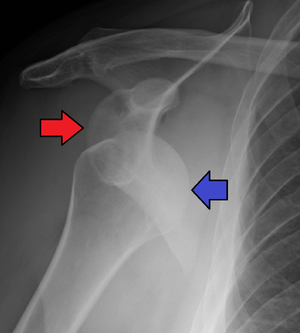

Anterior shoulder dislocation

- Shoulder dislocations account for 50% of all major joint dislocations, 90-98% are anterior[1]

- Arm held in abduction with shoulder lacking normal rounded contour

- Plain film X-ray of shoulder in at least 2 views (axillary lateral or scapular "Y" view important to show anterior vs posterior displacement of humeral head)

- Also need to rule out fracture-dislocation

- Bony injuries (Usually do not affect management unless there is an associated humeral neck fracture in which case bedside reduction is contraindicated):

- Hill-Sachs lesion (compression fracture of humeral head) - occur in up to 40% of cases; more likely with recurrent anterior dislocations

- Bankart lesion (injury to inferior glenoid labrum) - occurs in 10-20% of cases